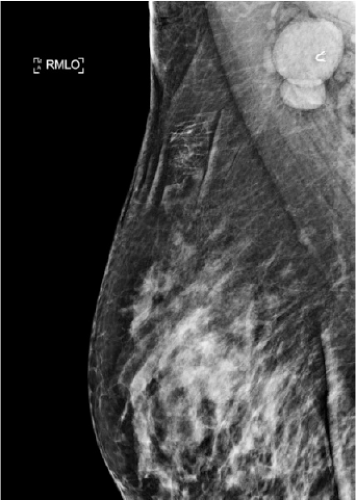

Imaging of the breast and regional lymph nodes should be obtained including mammogram and ultrasound (US) (Fig. 13-2). Core needle biopsy should be performed to acquire tissue from the primary tumor. The biopsy specimen also needs to be evaluated for hormone receptor (HR) status and HER-2 overexpression. For purposes of future treatment planning, a clip needs to be placed within the tumor. If abnormal-appearing lymph nodes are found on imaging, biopsy should be performed via fine-needle aspiration. If a dominant axillary node is biopsied a clip should be placed to identify this node at surgery.